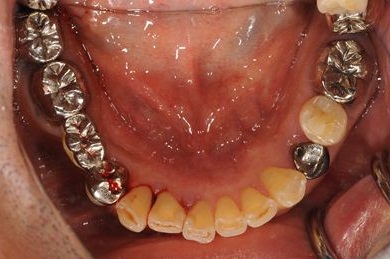

インプラントの症例写真 IMPLANT

骨再生インプラント治療

| 治療内容 | インプラント8本(GBR、ソケットリフト)、ハイブリッドセラミッククラウン17本(セラミック用土台5本) | ||||||||||||||||||||||||||||||||